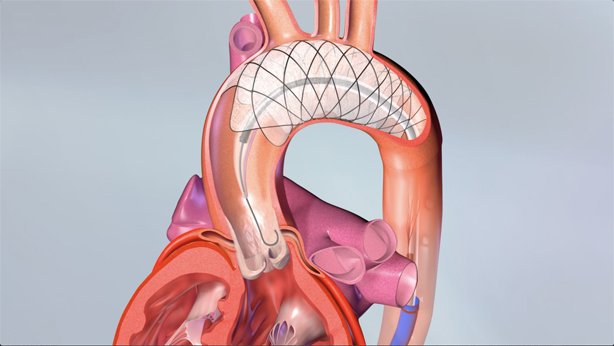

EnCompass F2 Device for cerebral embolic protection system in TAVR procedures

EnCompass Technologies

EnCompass’ F2 filter has pores small enough to block most emboli to the brain while preserving blood flow. During the TAVR procedure, 360-degree wall apposition of the filter in the aortic arch prevents migration. The filter, attached to a self-expanding, nitinol stent, is easy to insert, deploy and retrieve, according to the company. Copyright ©2021 KO Studios.